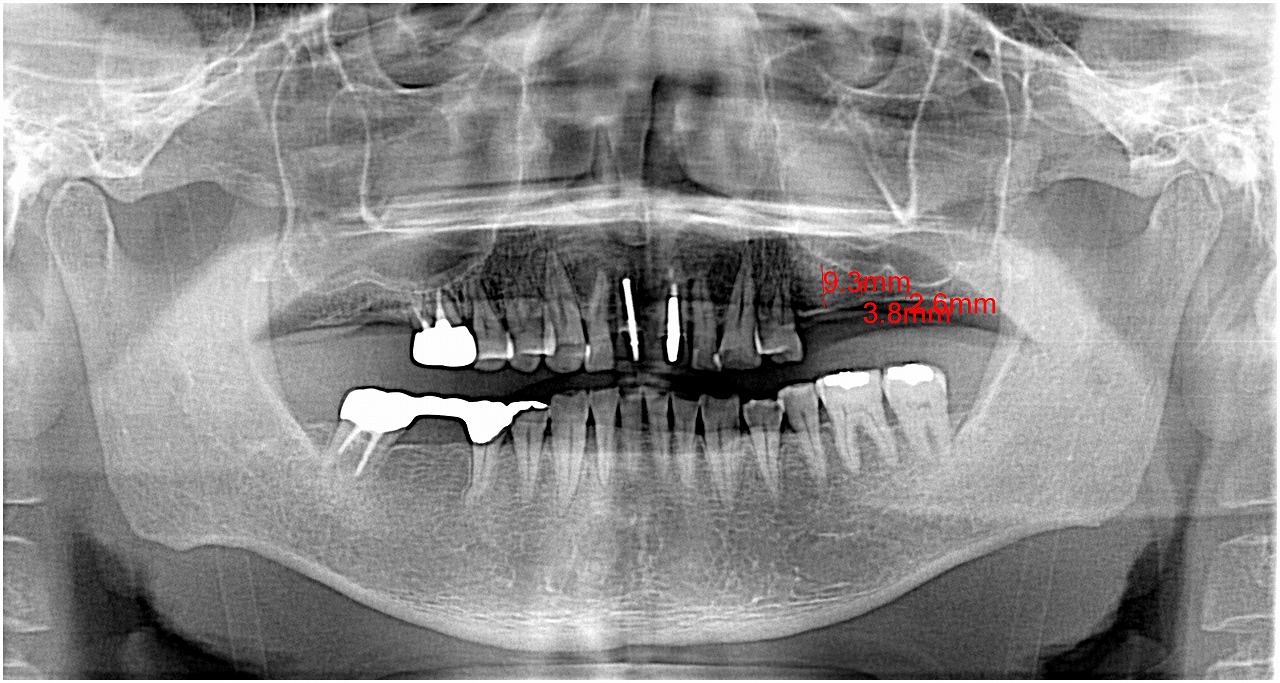

術前のパノラマになります